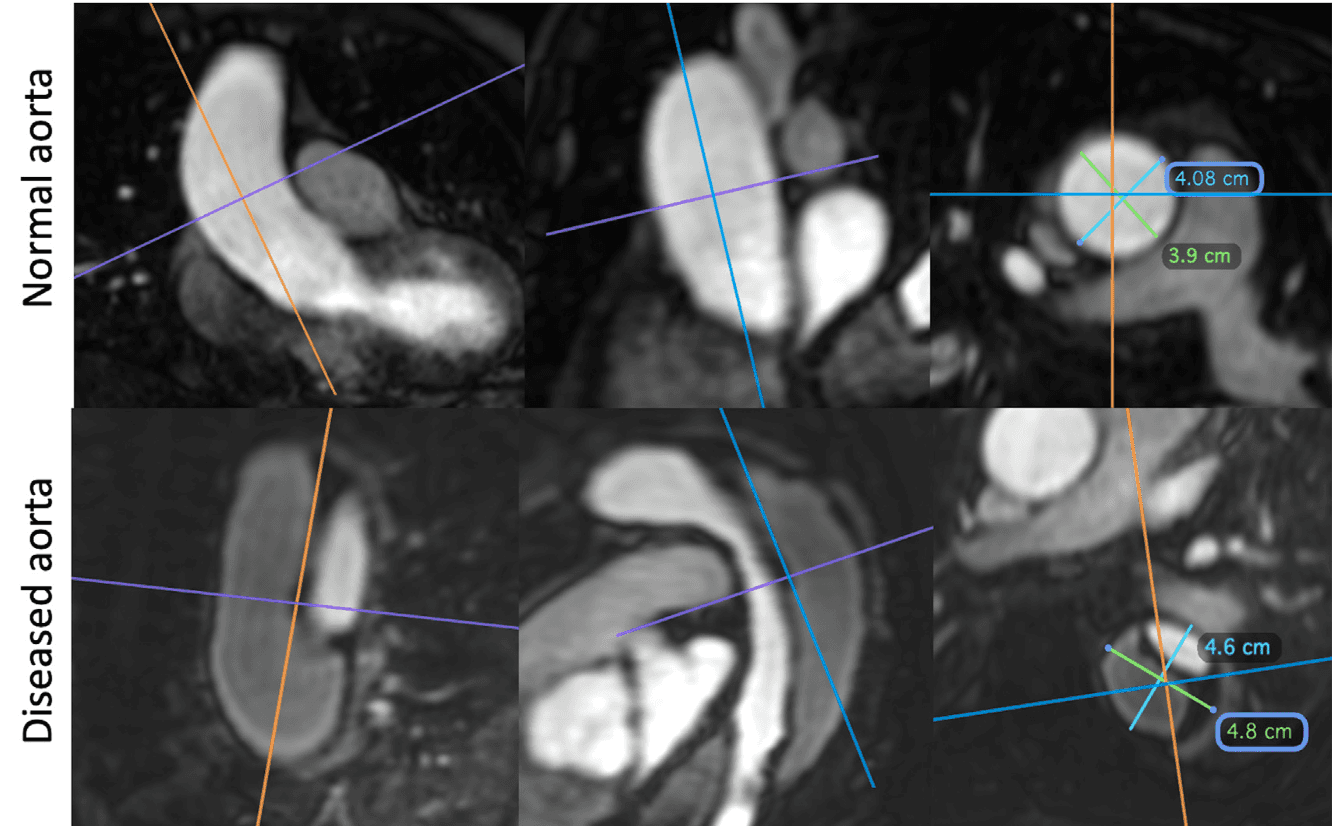

Un diámetro mal medido puede cambiar una decisión quirúrgica.

Las mediciones aórticas deben realizarse perpendiculares al eje longitudinal del vaso mediante reconstrucciones doble-oblicuas. En pared normal, el criterio recomendado es inner-to-inner; en enfermedad mural, outer-to-outer. Esta precisión técnica evita sobreestimaciones, mejora comparabilidad entre estudios y sostiene decisiones terapéuticas con mayor consistencia. En escenarios especiales, además, la RM ofrece una ventaja crítica: puede evaluar aneurisma, hematoma intramural o disección incluso cuando el contraste yodado está contraindicado, como en insuficiencia renal avanzada o alergia a contraste.